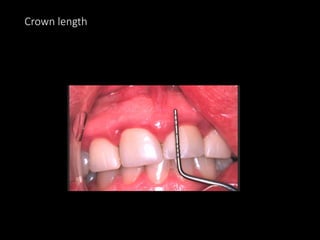

Crown length

Crown form